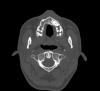

persona Опубликовано 12 октября, 2008 Автор Поделиться Опубликовано 12 октября, 2008 (изменено) Кроме того, проходил КТ. Выкладываю несколько срезов в области клыка. Изменено 12 октября, 2008 пользователем persona Ссылка на комментарий